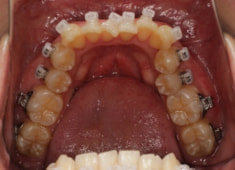

治療後(2年後)